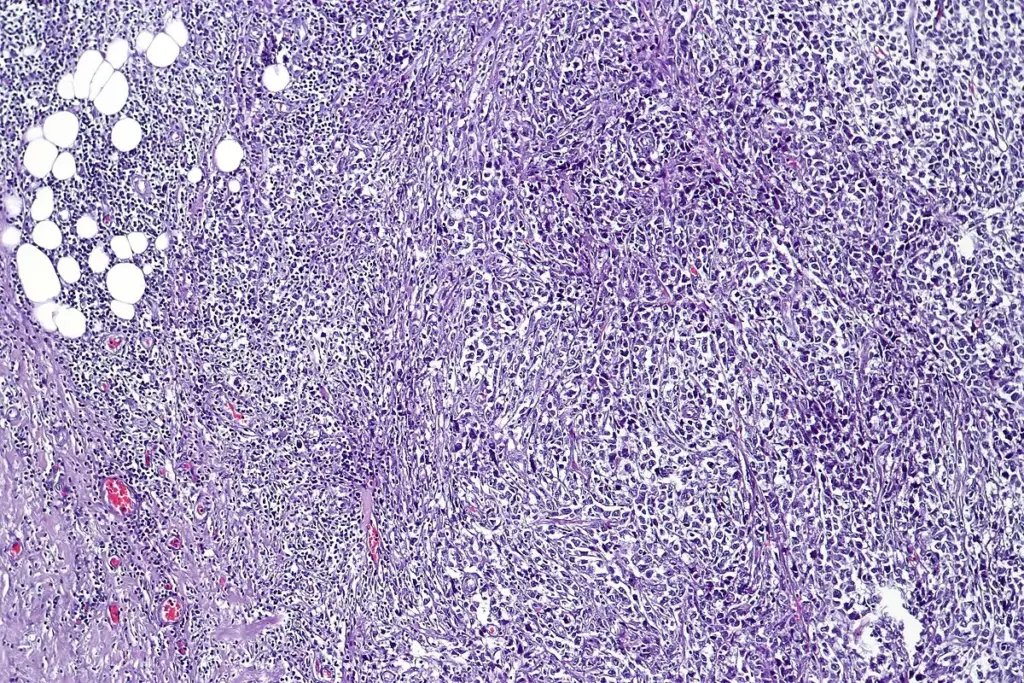

Sjögren’s syndrome is a long-term autoimmune disease where the immune system attacks the exocrine glands. It was once mainly known for causing dry eyes and dry mouth, but doctors now see it as a more complex condition called “autoimmune epithelitis.” This means the immune system targets the cells lining the salivary and tear glands. Normally, these glands make fluids that keep the mouth and eyes moist. In Sjögren’s, the immune attack damages these glands, leading to a major loss of their ability to produce moisture.

Regenerative medicine sees Sjögren’s syndrome as more than just a problem with the glands; it is a broader issue with the immune system. Both the body’s first-line and specialized immune cells, T-cells and B-cells, move into the glands and form clusters similar to those in lymph nodes. These clusters keep the inflammation going and cause more damage. New research shows that the gland cells themselves also play a role, sending signals that attract more immune cells and worsen the problem.